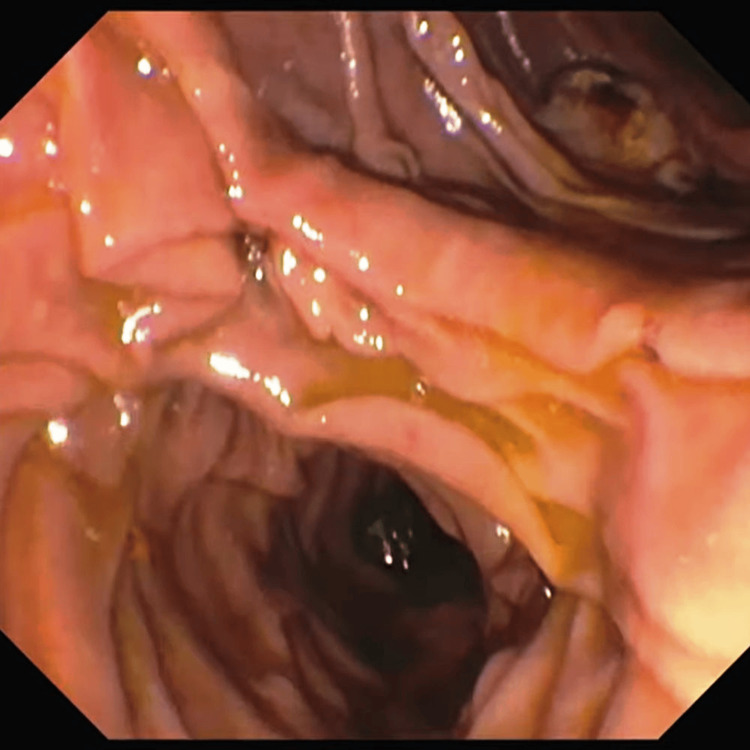

The complete stone clearance rate was higher in the LCBDE group compared to patients undergoing their first ERCP procedure (n=32; 88.89% vs. n=26; 72.22%), with an OR of 3.077 and a 95% CI of 0.864 to 10.954. Six patients in the ERCP group who had retained stones underwent repeat ERCP, as shown in Figure 1, while the remaining four patients underwent LCBDE. In the LCBDE group, two patients with retained stones underwent ERCP, and two underwent repeat LCBDE.

Trans-cystic LCBDE was performed in seven patients, and supra-duodenal choledochotomy was performed in the remaining 29 patients, as shown in Figure 2.